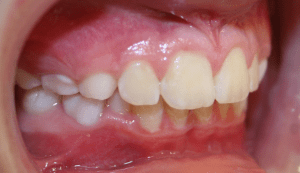

Before and After photos: Crossbite Treatment

Crossbite

A crossbite occurs when one or more of the upper teeth bite on the inside of the lower teeth. It can occur in the front of the mouth or on the sides, where its usually a bilateral condition. Early correction of a crossbite is recommended because it can lead to permanent problems including asymmetric jaw growth, irregular muscle function and altered tooth eruption.

Crossbite should be corrected because it can:

- cause premature wear of the teeth

- cause gum disease including bone loss

- cause asymmetrical development of the jaws

- cause dysfunctional chewing patterns

- make your smile less attractive

If there is a single tooth in crossbite, the tooth can be moved into the correct position with braces. When multiple teeth are in crossbite, the arch needs to be expanded with braces or a combination of braces and an intra-oral appliance. This will help correct the bite relationship and allow the jaws to grow in harmony.